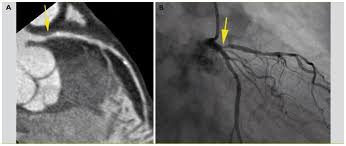

Ct le score calcique (ctcs) est une technique très sensible pour identifier et quantifier plaques athéroscléreuses calcifiées. Le score calcique coronaire est une évaluation chiffrée de l'étendue des dépôts athéromateux calcifiés observés au niveau des parois des artères du cœur, les coronaires.

Si d'une part le score calcique coronaire ne peut pas être. Quel est l'intérêt du score calcique coronaire en pratique clinique, et quelles sont ses modalités ? Le score calcique de chaque calcification dans chaque artère coronaire pour toutes les coupes tomographiques est ensuite additionné pour donner le score calcique total de l'artère coronaire (score cac).

Mm 2 ) ii est mesure sur l'ensemble des arteres coronaires apres une acquisition scanner faite sans injection d'iode et relativement peu irradiante (2 msv). On le réalise d'abord sans injection pour determiner le score calcique, puis avec injection de pdc. Lésion non quantifiable en cta sur une artère > = 2 mm à ct positif si dt.

Quantification du score calcique (calcium scoring).

Le score calcique de chaque calcification dans chaque artère coronaire pour toutes les coupes tomographiques est ensuite additionné pour donner le score calcique total de l'artère coronaire (score cac). Le score calcique coronaire est une évaluation chiffrée de l'étendue des dépôts athéromateux calcifiés observés au niveau des parois des artères du cœur, les coronaires. Le calcul du score calcique des artères coronaires (cac) permet de quantifierl'importance de la charge calcique des artères coronaires grâce à une tomodensitométriex « dédiée » induisant une faible irradiation.

Le score calcique est un parametre representatif de la quantite de calcification se trouvant sur le reseau coronaire. Artères coronaires rétrécies ou obstruées. Le score calcique est calculé de la manière suivante :

Le score calcique coronaire est une valeur indiquant le risque de développer un problème cardiaque. Résultats du score de calcium dans les artères coronaires. Le score calcique reflète le contenu en calcium des artères coronaires.

Le score calcique reflète le contenu en calcium des artères coronaires et donne ainsi un aperçu de l'athéroscélore (« encrassement ») des artères du cœur. Résultats du score de calcium dans les artères coronaires. Particularité d'évaluer la charge calcique globale question posée: